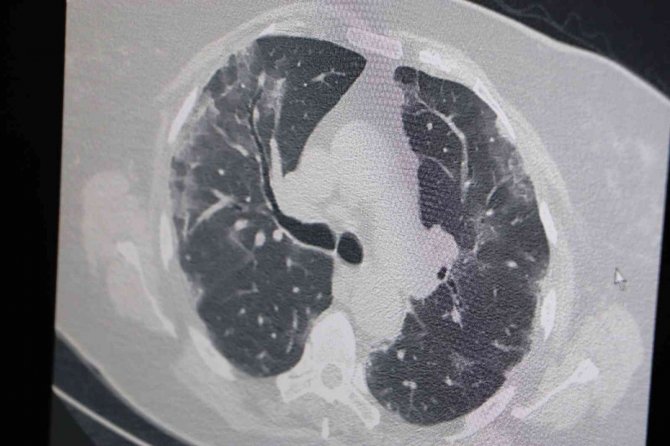

Covid-19 olan hastaların akciğer tomografilerini inceleyen Özkaya, "77 yaşında olan bir hastamız 4 doz Sinovac aşısı olmuş ama Covid pozitif olarak bize müracaatta bulundu. Hastada akciğer tutumu gözlendi. Orta derecede akciğer tutulumu olmasına rağmen tedaviyle tamamen düzelip taburcu oldu. 69 yaşında olan bir hastamız 2 doz Sinovac 2 doz da Biontech olmuştu. Hastamızda 77 yaşındaki hastamız gibi Covid pozitif ve akciğer tutulumuyla geldi. O da tedaviyle tamamen düzeldi ve taburcu oldu. Özellikle 2022 yılında aşı olmamış kişilerin Sinovac dahi olsa Biontech dahi olsa mutlaka hatırlatıcı dozlarını vurulmalarını öneriyorum" ifadelerini kullandı.